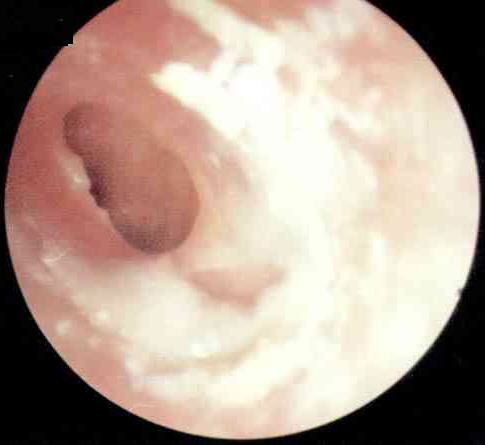

分泌性中耳炎

为什么会得卡他性中耳炎呢?

卡他性中耳炎,你了解多少?

鼻炎加听力衰退或由卡他性中耳炎诱发

分泌性中耳炎常见的问题

分泌性中耳炎是怎么一回事?